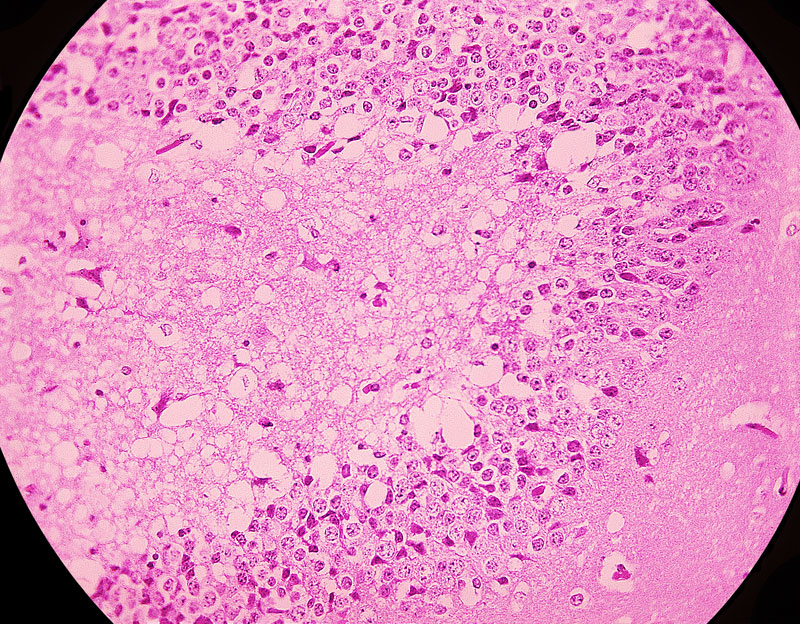

5、HE染色

蘇木精(Hematoxylin)和伊紅(曙紅,Eosin)染色法是組織學(xué)標(biāo)本及病理切片標(biāo)本的常規(guī)染色,簡(jiǎn)稱HE染色。經(jīng)HE染色后,細(xì)胞核被蘇木精染成紫藍(lán)色,多數(shù)細(xì)胞質(zhì)及非細(xì)胞成分被伊紅染成粉紅色。